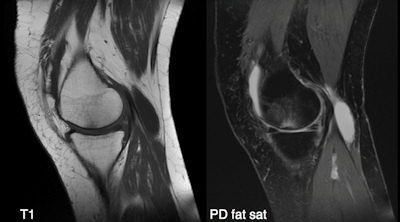

"The introduction of larger, more powerful devices (such as the iPad 2) is likely to further expand this kind of application, with some surgeons already using it in the operating room to assist interventions," Faggioni said. For instance, the following images of CT pulmonary embolism and knee MRI, as well as the chest CT image of lung nodules above were exported from an iPad 2. "Diagnosis could have been made on it without the need of a workstation," he said.